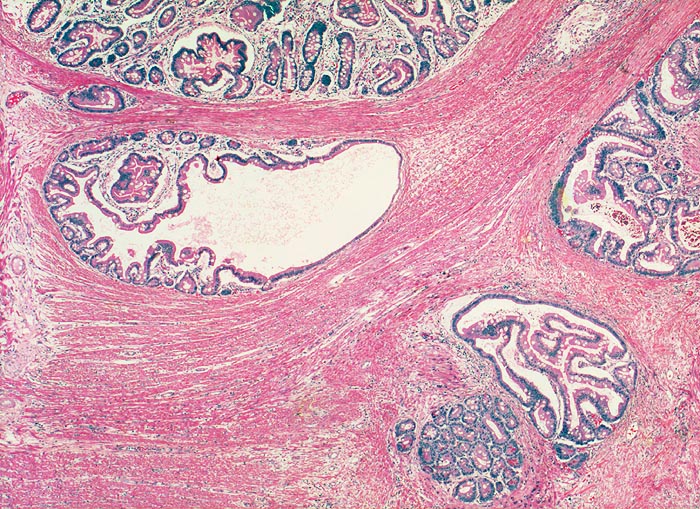

AP/ Peutz-Jeghers Polyp, Dünndarm

Peutz-Jeghers Polyp, Dünndarm

Diagnose Gruppe

Topographie Gruppe

Jejunum